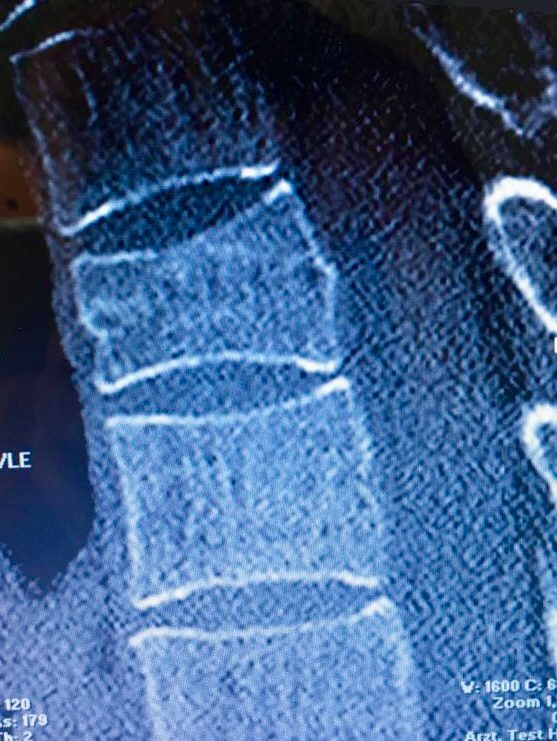

Ein 48-jähriger Patient leidet seit sechs Monaten an chronischen thorakalen Rückenschmerzen mit Ausstrahlung in die rechte Schulter nach einer BWK4- Deckplattenkompressionsfraktur, die er sich bei einem Mountainbikesturz zugezogen hatte. Die Fraktur wurde zunächst konservativ mit Schmerzmitteln nach WHO-Schema behandelt. Nach sechs Wochen konnte er bei stabiler Knochensituation und erfolgter MRT-Kontrolle mit Physiotherapie beginnen und wieder eingeschränkt in den beruflichen Alltag eingegliedert werden. Stoß- und Sprungbelastungen wurden für zwölf Wochen gemieden. Nach sechs Monaten plagten ihn immer noch anhaltende, mittlerweile chronische Rückenschmerzen, die zudem nun in die rechte Schulter ausstrahlten. Ein sensomotorisches Defizit wurde verneint. Er hatte einen hohen Leidensdruck, nachdem er selbst im normalen Alltag Schmerzen auf einer visuellen Analogskala von 7/10 angab und seiner Leidenschaft – dem Radfahren – nicht mehr nachgehen konnte. Wegen unerwünschter Nebenwirkungen hatte der Patient seine Schmerzmedikation mit Ibuprofen und Tilidin retard bereits nach drei Monaten beendet.